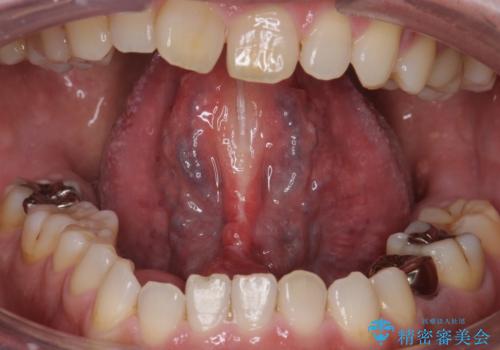

術後1週間で抜糸、約2週間で完全に治癒していきました。

切除後は特にラ行が言いやすくなったそうで大変喜んでいただけました。